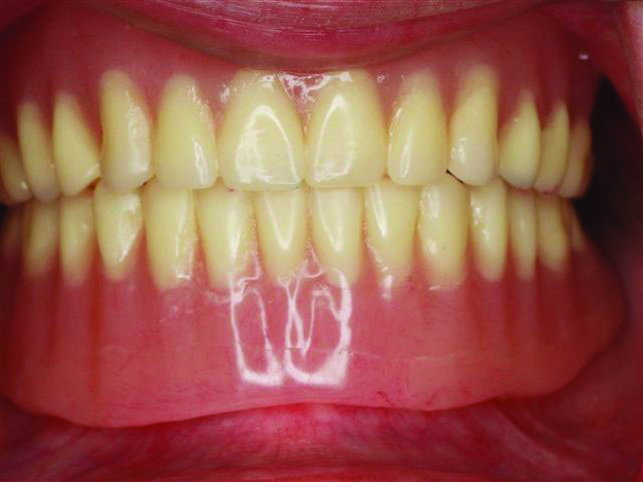

Fig 4. Set-up try-in verifying fit, borders, bite, and tooth position.

Figure 4

Fig 5. Set-up try-in to verify esthetics and phonetics and make adjustments as needed to tooth position.

Figure 5

For the next appointment, the dentist receives a denture set-up to try in. Here is the final chance to make any substantial changes to the denture. The dentist verifies the fit, esthetics, vertical dimension, and phonetics (Figure 4 and Figure 5) to ensure that the patient can speak, verify the tooth shape, and select the shade. Because the set-up is normally in wax, there is wide latitude to make changes in position, fit, and feel for the patient. Once both patient and dentist are satisfied, the set-up is returned to the laboratory for final processing. On the laboratory side, after processing, the dentures should be checked again to ensure no changes happened during the process and are returned to the dentist ready for insertion.3,4